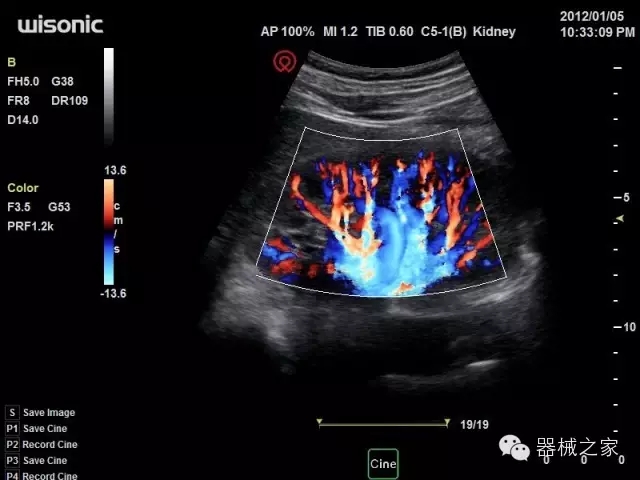

臨床圖片賞析

產(chǎn)品特點

·全球目前唯一一款配備主機雙探頭接口,整機重量(含電池)在5公斤以內(nèi)的便攜式彩超;

·獨有的HoloTM PW 實時3取樣門PW成像技術(shù),精確進(jìn)行血管診斷;

·一鍵優(yōu)化B、Color、PW,Auto Doppler自動識別血管位置、偏轉(zhuǎn)角度等,提高工作效率;